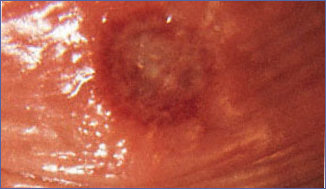

Gelişmekte olan ülkelerde düşük sosyoekonomik durumda ve kötü hijyen koşullarında yaşayan sünnetsiz erkeklerde daha sık görülür. Belirti vermeyen yaraları ve birden çok cinsel eşi olan kadınlar önemli kaynaklardır. HIV'ın (AIDS) heteroseksüel yolla yayılımını kolaylaştırır. Hemophilus ducreyi adlı bakterinin etken olduğu hastalık zemini kızarık ufak kabarık bir lezyon olarak kendini gösterir. Lezyonun etrafı kırmızı bir halka ile çevrilidir, yumuşak tabanlı bir delik ile nekrotik bir ülser şeklindedir. Lezyon aşırı hassastır ve lezyonların %50'sinde iltihabi lenf bezi şişliği (bubo) vardır. Bunun değişim göstererek sonunda ağrılı sert olmayan bir zeminde gri ölü bir zarı olan çevresi şiş yaralar halini alır. Genellikle 1-3 adet yara olur. Ağrılı idrar, vajinal akıntı ya da kanama, kasıklarda şişkinlik, meme ve parmaklarda da tutulum görülebilir. Ağrılı kasık lenf bezi şişliği de tipiktir. Tek taraflı yada çift taraflı olabilir. İlerleyip fluktuasyon(dalgalanma) veren apse haline gelirler (bubo). Tanı mikroskopta balık sürüsü görünümlü bakterilerin görülmesi, kültür (%70-80 duyarlı) ve karanlık alan mikroskopisi ile konur. Serolojik kan testleri yapıldığında HIV ve sifiliz; dermatolojik testler yapılarak kanser dışlanır. Tek doz oral 1 g azitromisin (veya ceftriaxone) tedavi edicidir. Eritromisin de kullanılabilir, daha ucuzdur. Yedi gün sonra kontrole çağrılır. Cinsel eş de tedavi edilmelidir.